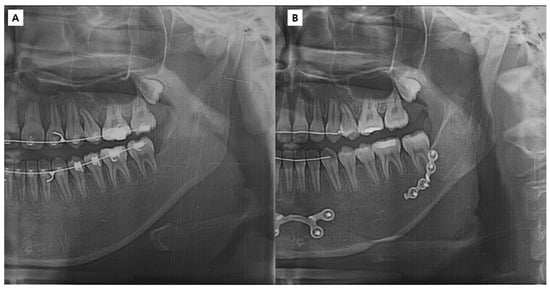

2.2. Virtual Surgery (VS), Designing and Creating Patient-Specific Materials, and Actual Surgery

2.2.2. Surgery